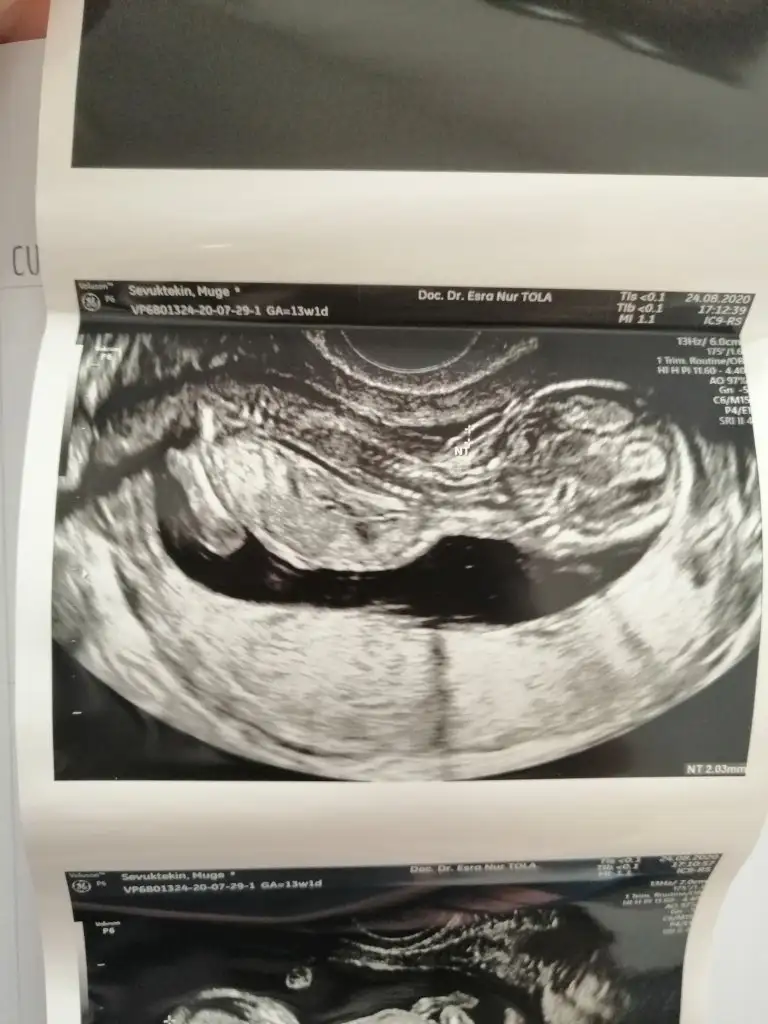

Maşallah canım seninki göstermemek için elinden geleni yapmışBen de bugün doktora gittim. Bebek iyi çok şükür sağlıklı. Folik asiti hala kullanıyordum onu bıraktım. Ama başka bir vitamin başlamadıkkan değerlerim normaldi en son ondan olabilir diye düşündüm ama yeni test yaptırmadım doktor istemedi. Cinsiyeti öğrenemedim henüz. Ultrasonumuz bu ama göstermiyor Eki Görüntüle 2679812